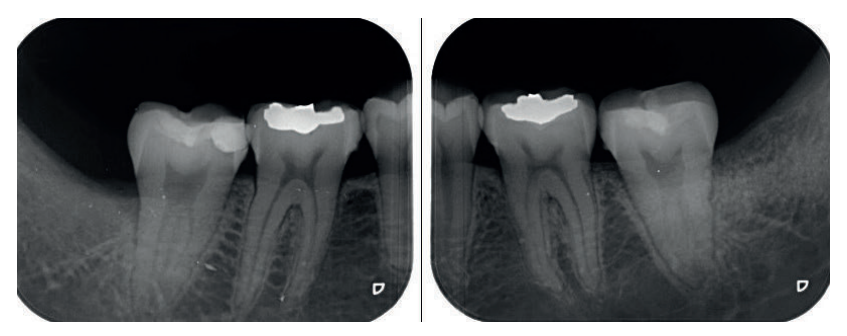

Se retiró la sutura de nuevo a la semana, y se realizaron revisiones a los 3 y 6 meses, donde se midió la profundidad de sondaje (Tabla). Se realizaron radiografías periapicales a los 3 meses (Figura 9) y a los 6 meses (Figura 10).